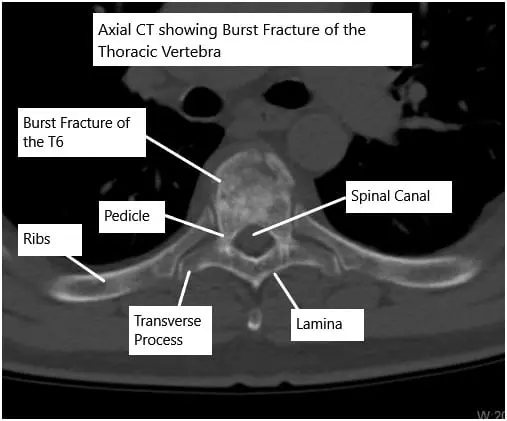

CT scan of the thoracic spine showing a burst fracture of the T6 vertebra.

- CT scans: Provide detailed images of bone fragments and fracture patterns.

- Burst fractures: The vertebra shatters into multiple pieces, sometimes pressing into the spinal canal.